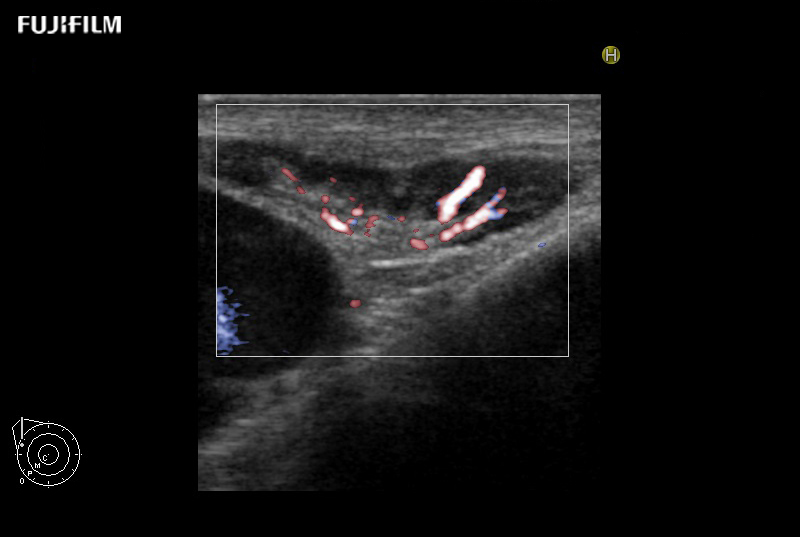

DFI is a new imaging technology for visualization of low velocity blood flow with greater resolution and sensitivity below the previous detection threshold.

Provides clearer delineation between tissue and blood flow compared to conventional Color Doppler. Even low velocity flow can be imaged with high sensitivity.